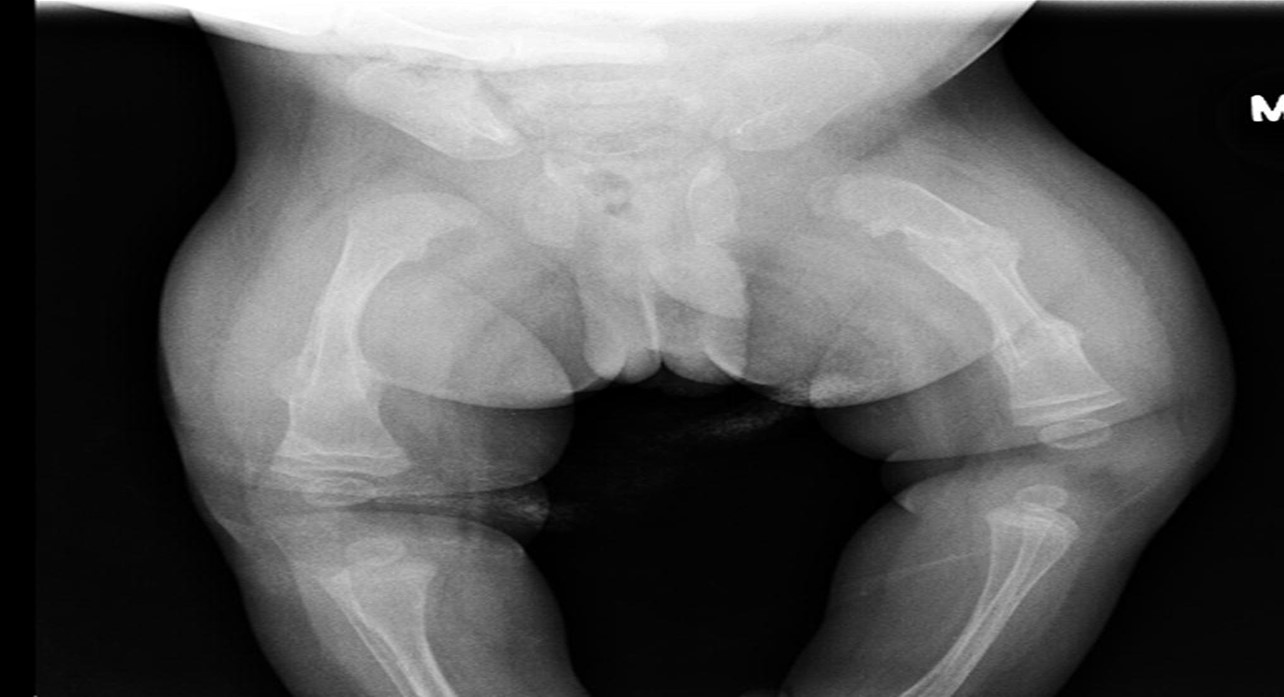

This condition, also known as brittle bone syndrome, is another example of a diverse collection of genetic disorders that are characterized by bones that are prone to bending and breaking readily. A common symptom of the condition is a delay in the healing of wounds, as well as a rotated and twisted spine, which can give the appearance of having a "humped-back" (kyphotic). Osteogenesis imperfecta tarda is the medical term for type I osteogenesis imperfecta. The sickness is the result of a reduction in the formation of 1 and 2 chains. Fractures that are the result of mild trauma appear in early childhood. A diagnosis of this condition can be made using prenatal ultrasound imaging that reveals bowing of the long bones or fractures. The most severe form of osteogenesis imperfecta is type II, also known as osteogenesis imperfecta congenita. Patients with pulmonary hypoplasia don't make it past the uterine or newborn stages of the disease. The majority of people who suffer from severe OI have mutations in the gene that codes for either the pro-1 or pro-2 chains of type I collagen. The majority of mutations result in the substitution of amino acids with bulky side chains for glycine residues (in the form –Gly–X–Y–). The structurally aberrant pro- chains that develop as a result of this process hinder the creation of the necessary triple-helical conformation.<br /><br />By: Asst. Lec. Ahmed B. Mahdi